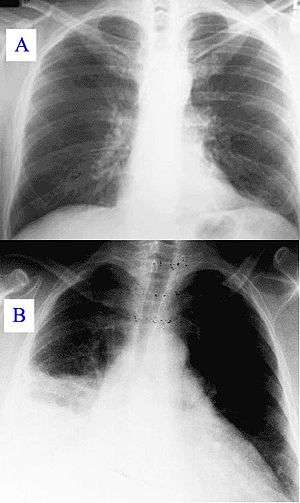

During its course, the disease can progress to an atypical pneumonia, which can result in a life-threatening acute respiratory distress syndrome, whereby such symptoms usually occur during the first four to five days of infection.